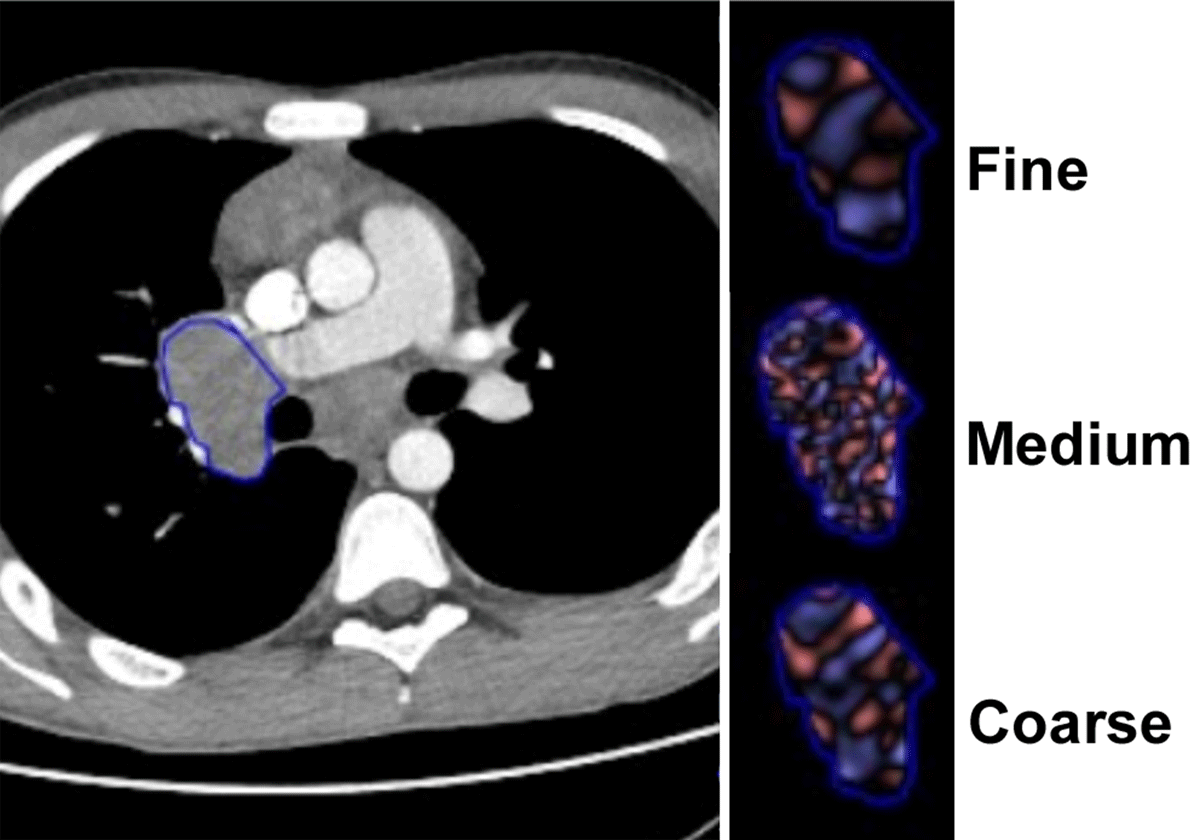

Figure 2

CT images in 15-year-old young women with Hodgkin’s lymphoma stage IV. Illustration of the pulmonary lesion delimitation, image filtration.